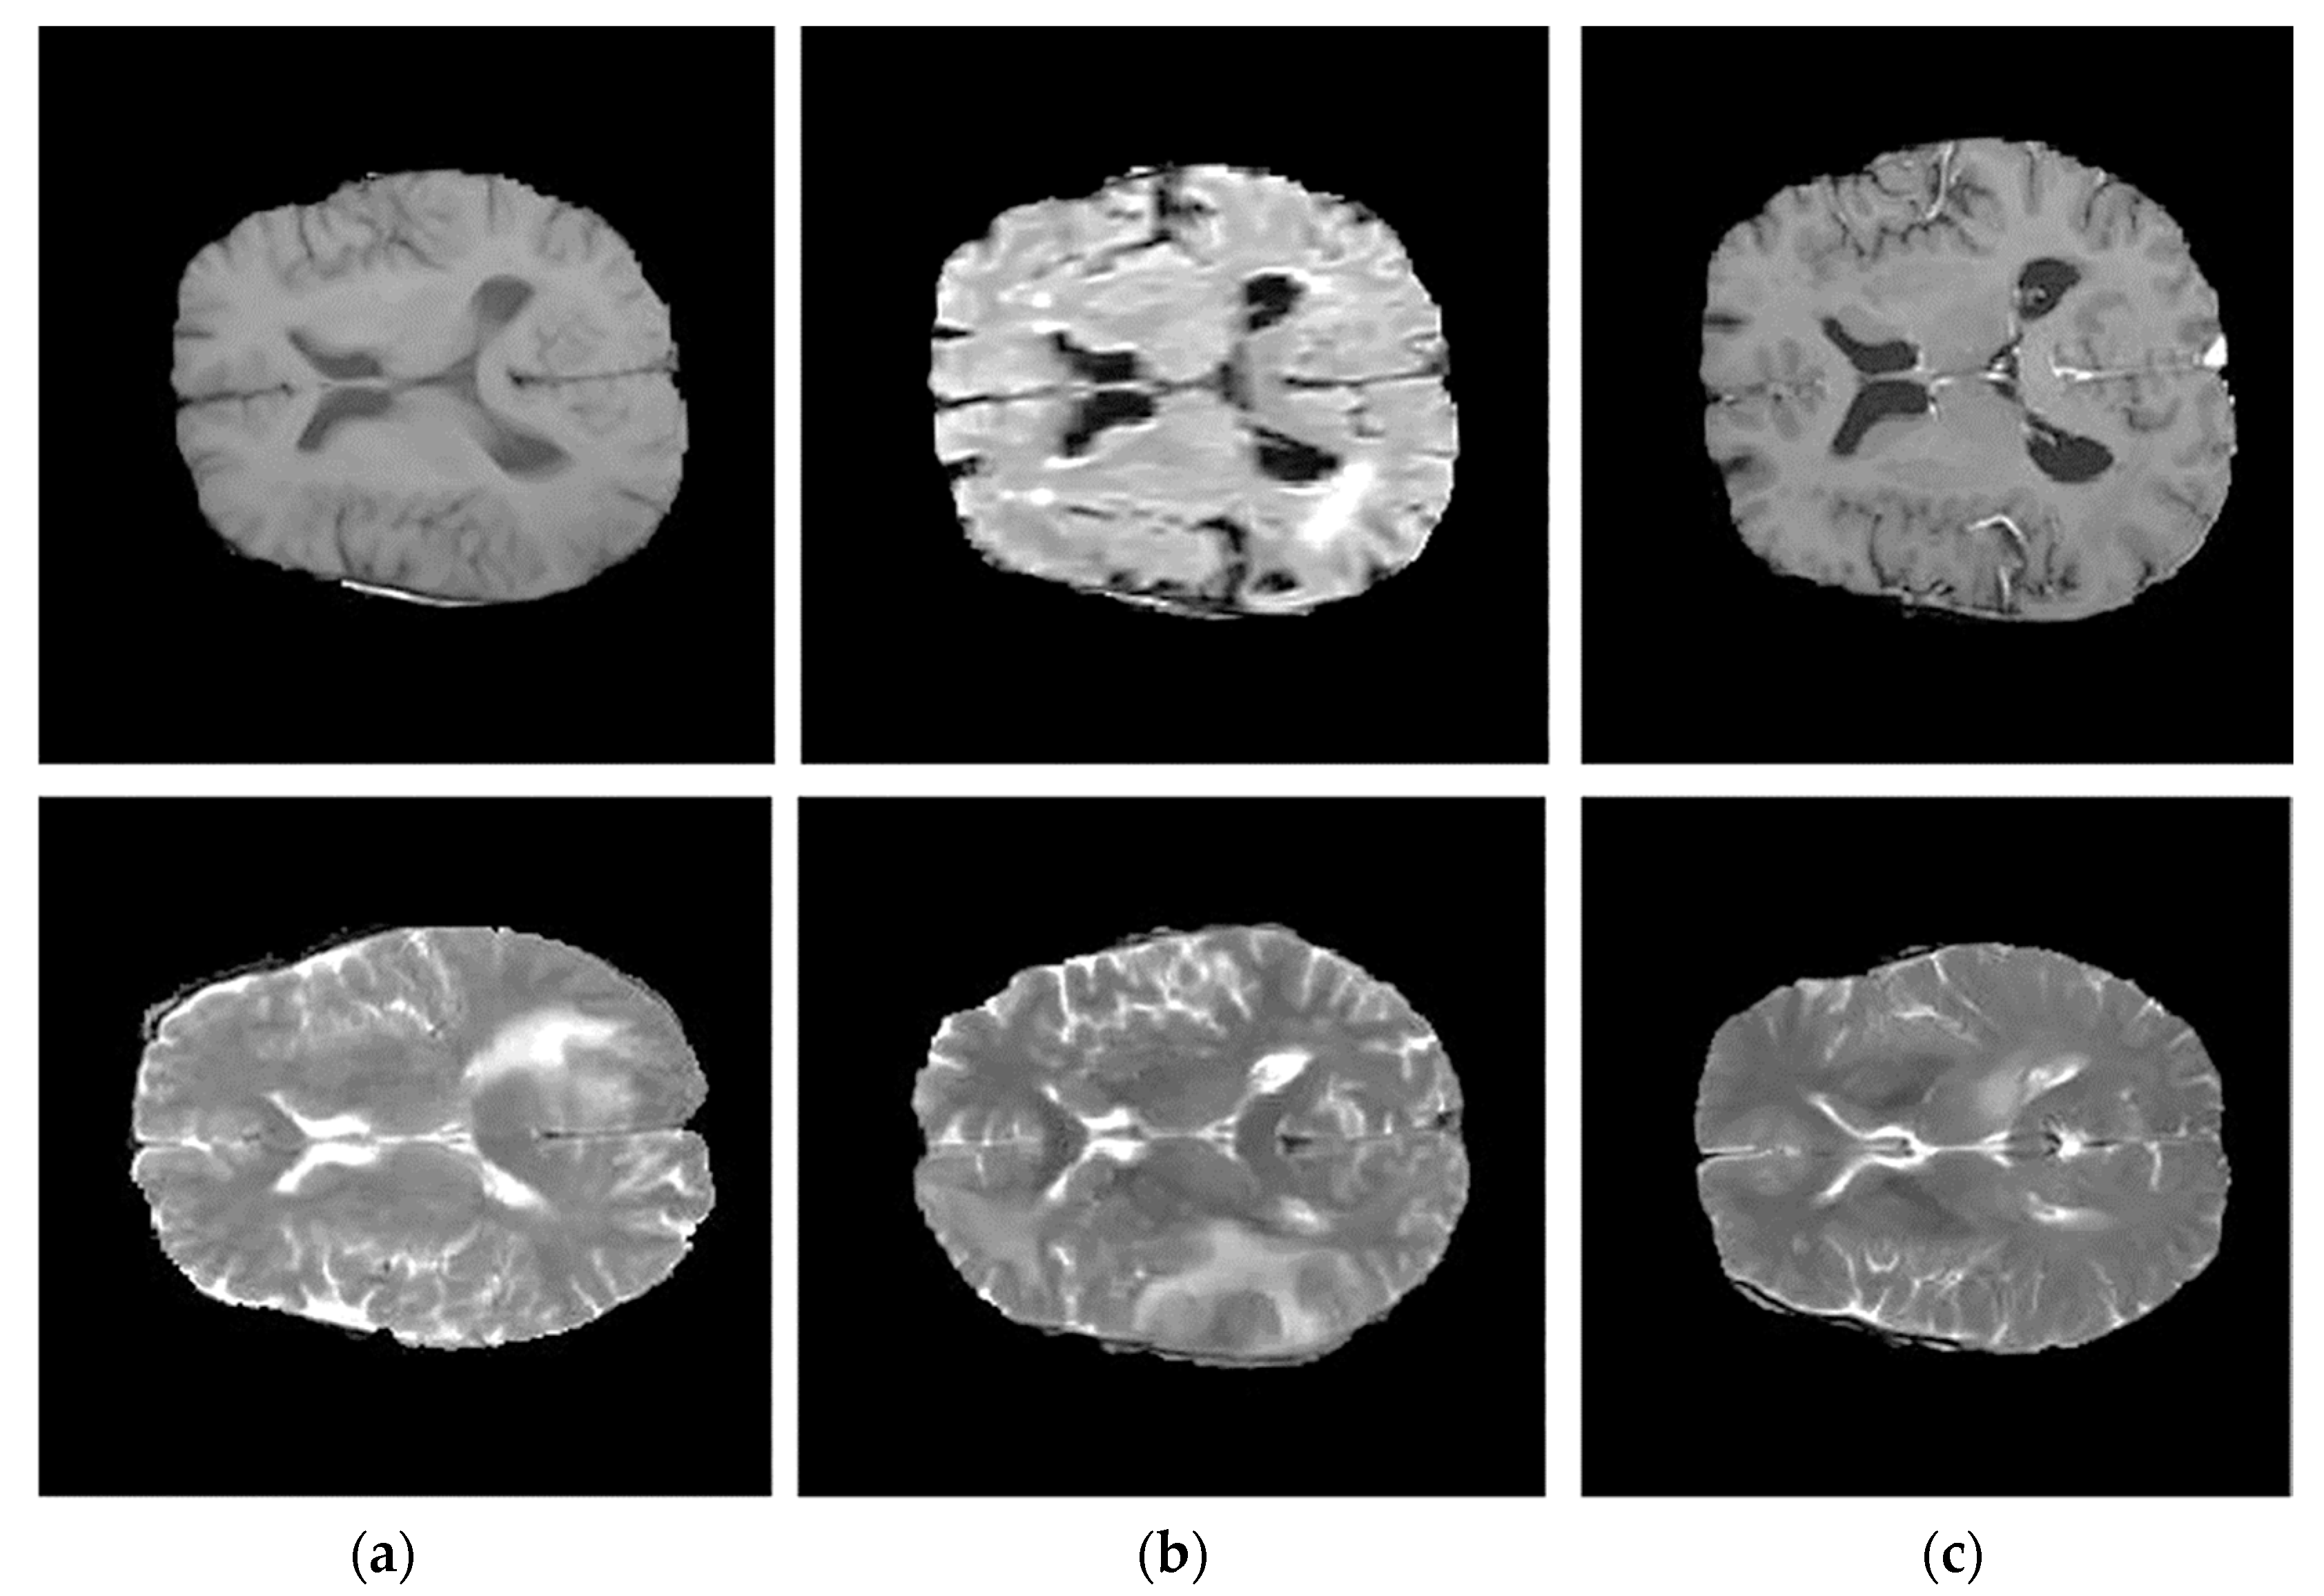

3.1. Step 1 Preprocessing Phase

- Groza, V.; Tuchinov, B.; Pavlovskiy, E.; Amelina, E.; Amelin, M.; Golushko, S.; Letyagin, A. Data preprocessing via multi-sequences MRI mixture to improve brain tumor segmentation. In Proceedings of the International Conference on Bioinformatics and Biomedical Engineering, Granada, Spain, 6–8 May 2020; Springer International Publishing: New York, NY, USA, 2020; pp. 695–704. [Google Scholar]